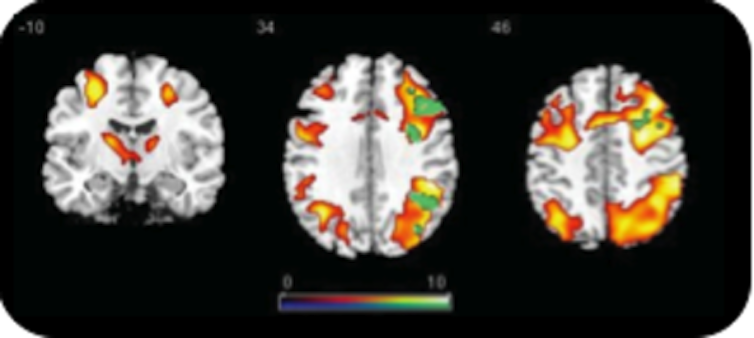

Subtract the patterns from each other, do some more statistics, and the result is a neat coloured blob on a picture of the brain.

Going from the magnetic pulses to the coloured blobs is fraught with methodological and statistical choices that can completely change what the blobs will look like.

That’s because mental states and brain areas do not have a one-to-one relationship. And all the variability this causes generates scepticism.

But stable patterns of blobs are evident and a lot of the variability seems due to subtle differences in tasks and experimental designs. Nevertheless, there’s still serious discussion about the best method of brain scanning and no doubt many findings from the first 20 years of fMRI will not survive the next 20.

On the basis of the brain map, researchers have begun to formulate possible models of brain mechanisms – which blobs cause which other blobs.

The time-course of brain activity allows us to rule out some mechanisms and rule in others. This way, we learn how mental states are built up, emerge from sensory input, and how they lead to behaviour.

In other words, the blobs don’t explain the mind, but their causal interconnections and the underlying statistical analysis may.